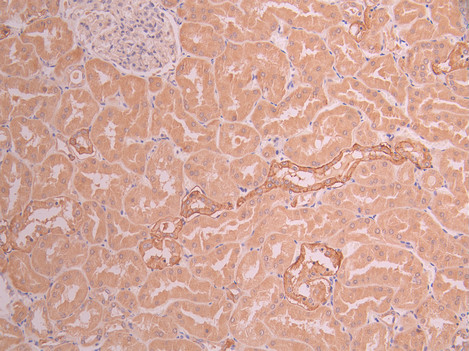

IHC image of CSB-RA981161A0HU diluted at 1:100 and staining in paraffin-embedded human kidney tissue performed on a Leica BondTM system. After dewaxing and hydration, antigen retrieval was mediated by high pressure in a citrate buffer (pH 6.0). Section was blocked with 10% normal goat serum 30min at RT. Then primary antibody (1% BSA) was incubated at 4°C overnight. The primary is detected by a Goat anti-rabbit polymer IgG labeled by HRP and visualized using 0.05% DAB.